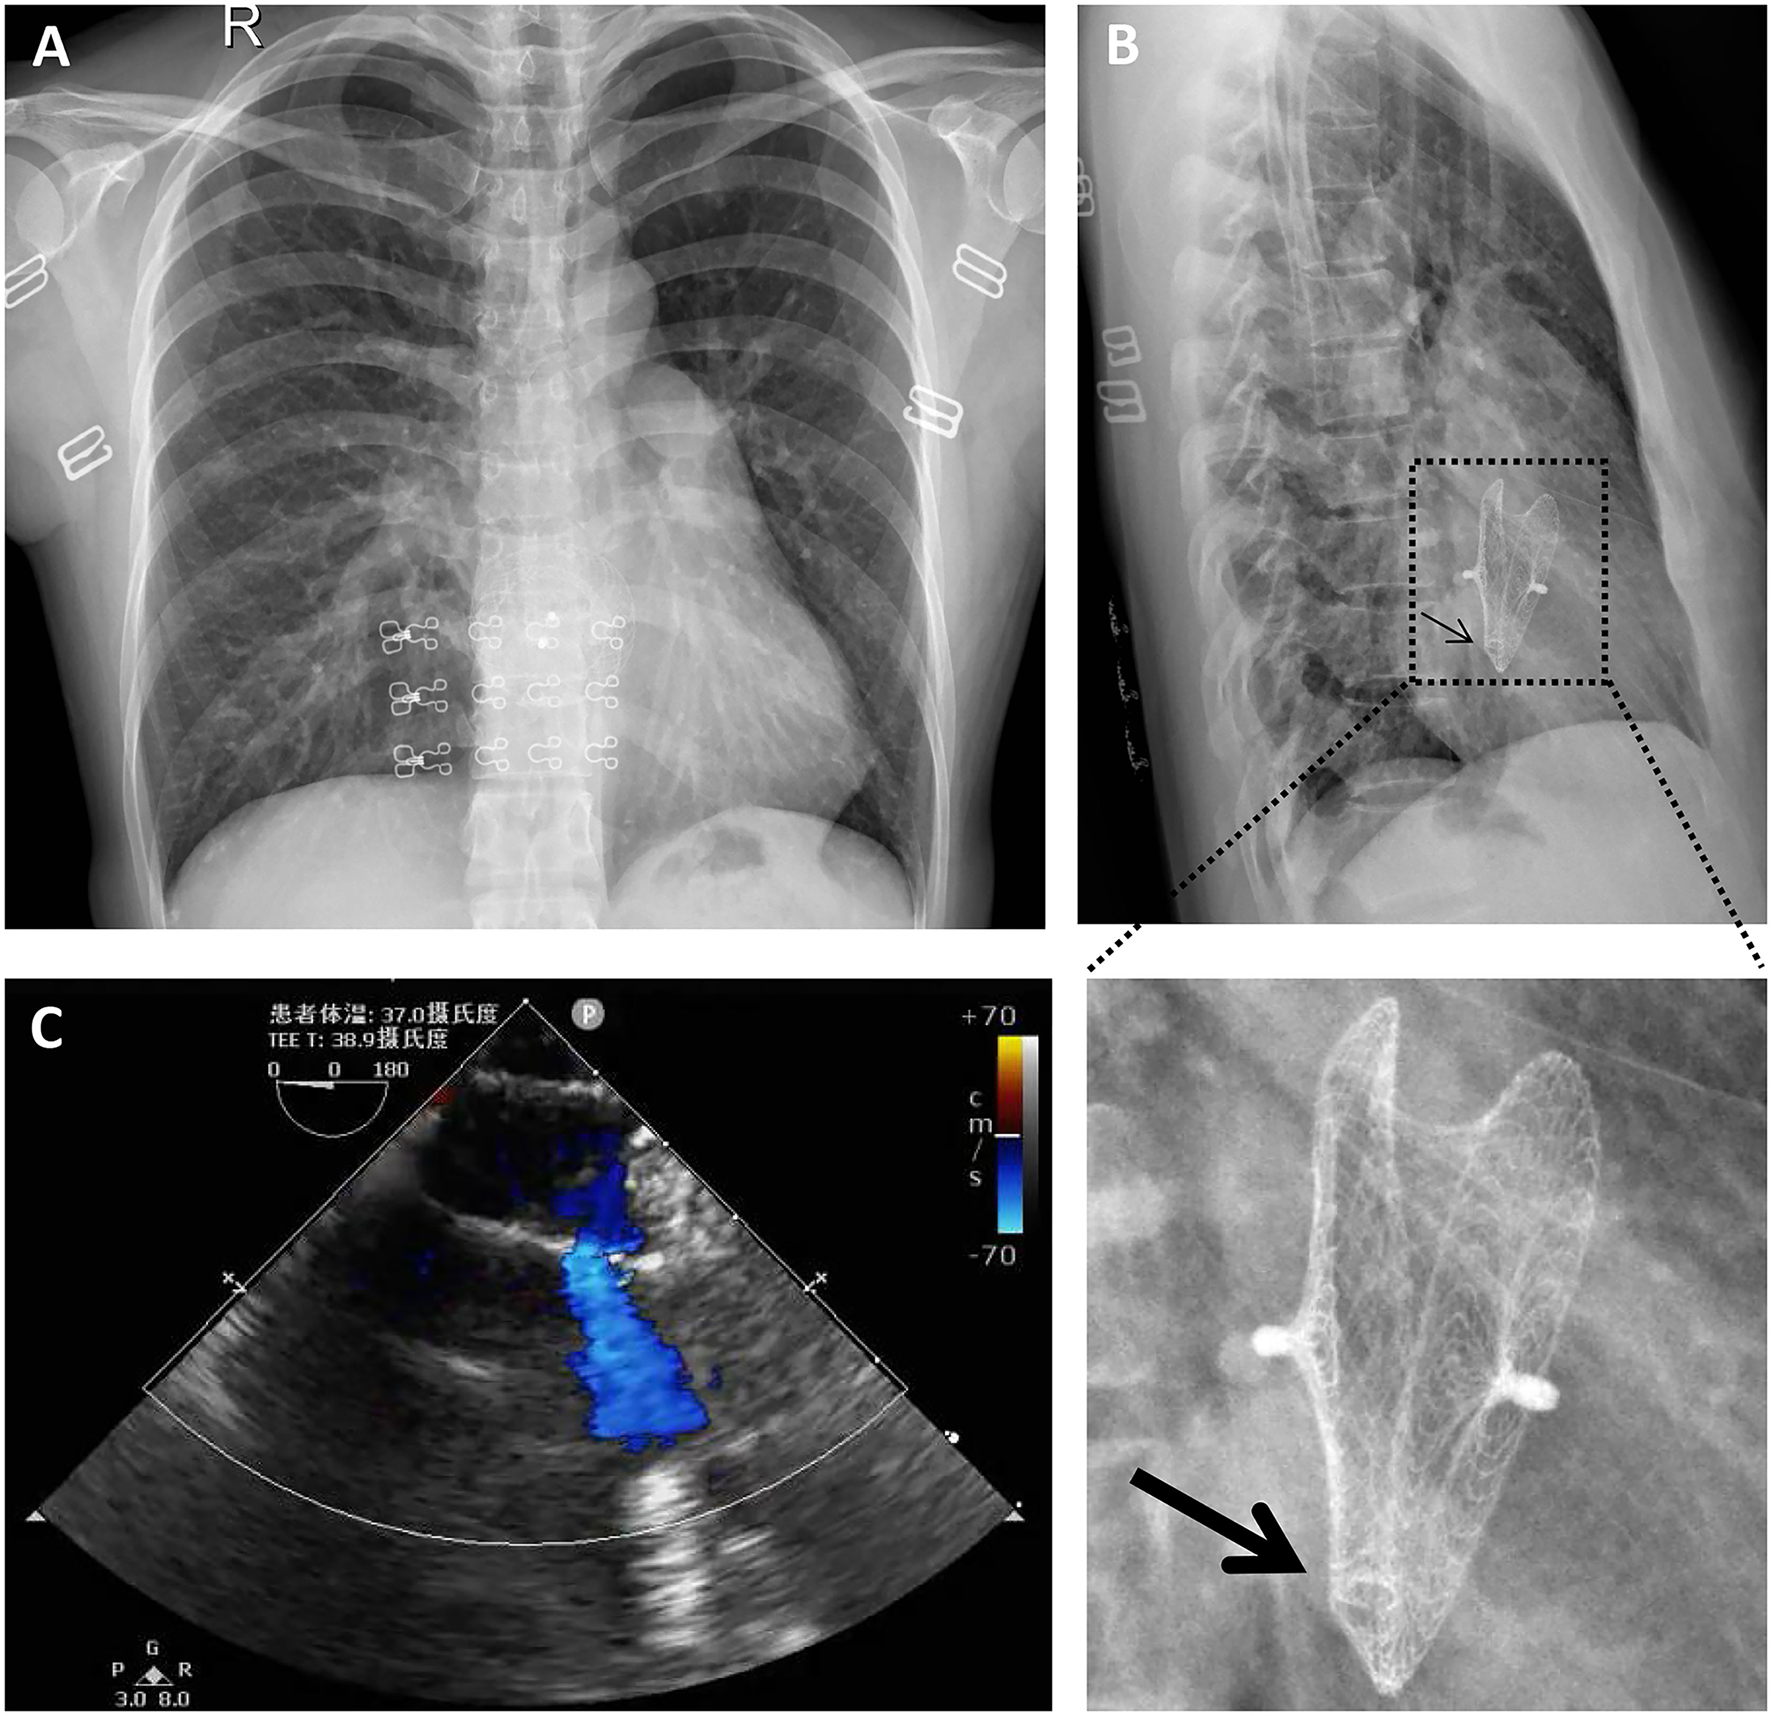

A 40-year-old female with sudden syncope was referred to our department. She has an 18-year history of percutaneous ASD (30 mm in diameter) closure with a 40-mm mushroom umbrella occluder (Huayi Shengjie Co., Ltd., Beijing, China). The surgical result was satisfactory, and no residual shunt was seen. Regular re-examination 3 years after the operation showed no abnormality. Two cesarean sections after 4 and 7 years of percutaneous ASD closure and a hysteromyoma surgery after 13 years of percutaneous ASD closure had been done. Transthoracic echocardiography and electrocardiogram during these three hospitalizations showed no abnormality. The patient in our case has not been followed up and had not undergone transthoracic echocardiography for the last 5 years. In the past 3 months, the patient had two episodes of sudden syncope, one was induced by exercise, and another had no obvious incentive, accompanied by sweating and pale complexion, which was relieved spontaneously in about 5 min. She denied chest pain, chest tightness, shortness of breathing, and palpitations. On physical examination, a soft blowing murmur was heard in the second and third costal margin of the left margin of the sternum. There were no other notable clinical findings during a physical examination and no medical, family, or psychosocial history including genetic information about cardiovascular disease. X-rays (Figures 1A,B) showed that most parts of the closure were deformed, especially the left atrial side (Figure 1B, arrow) and that the nitinol frame of the occluder was not displaced and there was no evidence of a frame fracture. The electrocardiogram demonstrated sinus rhythm and an incomplete right bundle branch block. Transthoracic echocardiography revealed a recurrent significant multi-bundle left-to-right shunt through the device and small adhesions were visible on the occluder (Figure 1C). Moreover, the enlarged right heart chambers and mild mitral valve regurgitation were detected. The patient was eventually diagnosed with a late-onset residual shunt of transcatheter device occlusion of ASD (occluder recanalization).

Figure 1. Chest radiography (A,B) and transthoracic echocardiography (C) preoperatively indicated that most parts of the closure were deformed, especially the left atrial side [(B), arrow]; a significant multi-bundle left-to-right shunt through the device and a small adhesion on the occluder was detected (C).

Considering the multiple perforations of the occluder with an unusual irregular surface of the discs (Figure 1B), and after a careful discussion with the patient and her family, an open heart surgery was scheduled and performed. A standard median sternotomy incision was performed. The aorta was then cannulated, followed by separate cannulas placed in the superior vena cava and inferior vena cava. After full heparinization, cardiopulmonary bypass (CPB) was routinely applied. The aorta was cross-clamped, and a cold cardioplegic solution (Del Nido) was instilled via the aortic root to arrest the heart. After the right atrium was opened, the initialized tissue of the failed occluder was sufficiently freed, the occluder was then released and completely removed, and a bovine pericardial patch was used to reconstruct the atrial septum. During the operation, most parts of the closure were deformed (Figure 2), especially the left atrial side closed to the edge of the pulmonary vein, which resulted in the possible cause of late-onset residual shunt. The PVA membranes showed multiple perforations and were partly dissolved, the diameter of the largest void was around 10 mm, and the left atrial side of the occluder was damaged more obvious than the right (Figure 2B, arrow). No thrombus and other vegetations were seen. Furthermore, according to the pathology report (Figure 3), the surface of the occluder has not been fully epithelialized, instead, there was an extensive proliferation of fibrous collagenous tissue. This may have been due to the constant flow of blood. The implanted device did not show evidence of infection, and the bacterial cultures were negative. Finally, the patient recovered uneventfully without recurrent syncope and residual shunt (Figure 4).